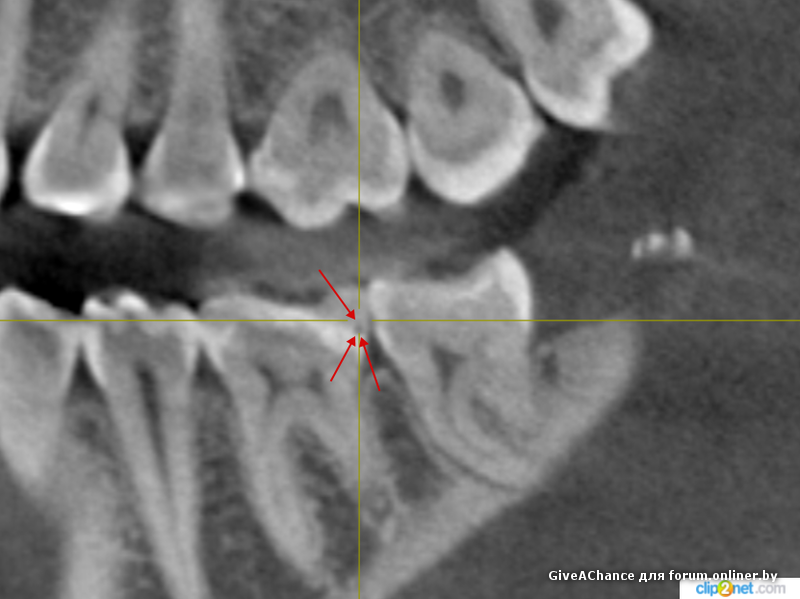

Tatsianka_M:

Выложи скриншоты КЛКТ со стрелками, если ЧЛХисты показывали, в каких именно местах они увидели гранулемы.

баламутище:

Ну не знаю... Почему-то члх на кафедре на этом КЛКТ меряет на 26 гранулему в районе 2 мм. На 28 зубе один канал недопломбирован на 4.1 мм. И там гранулема не уменьшается. У меня нет ощущений на 5 звезд.

И какая разница, ремонтируем авто или зубы? Ремонтники авто показывают неисправные детали и механизмы. Так чем стоматологи отличаются от ремонтников? Пусть показывают неисправности, есть же КЛКТ. Они показывали тебе на КЛКТ гранулемы?

# 20 мая 2016 00:18 Редактировалось Неизвестный кот, 1 раз.

Показали и померяли при мне. Мне же сейчас надо раскрывать диск и пробовать найти тот срез, и не факт, что найду. У нас на консультации стоматологи как-то не выкатывают лист с письменным заключением и скриншотами.